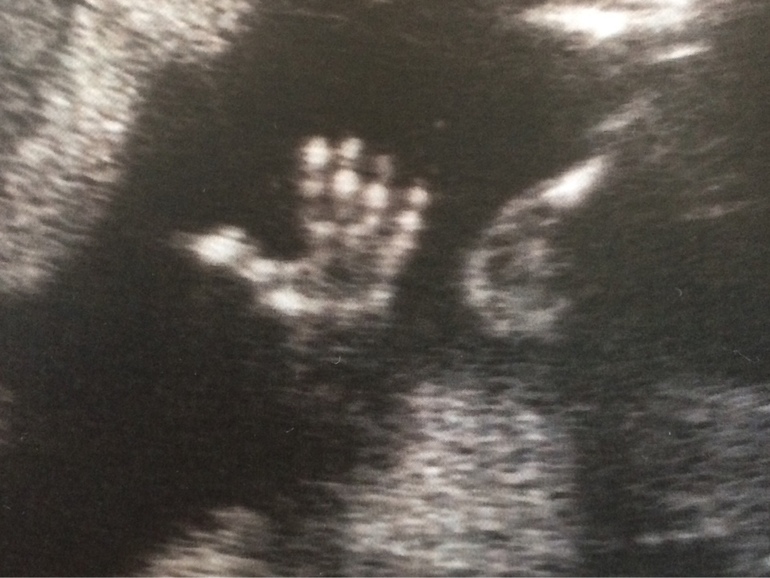

Передо мной и мужем отдельный монитор, сразу появилась картинка, доктор сначала показала вид сбоку, потом сразу приступила с замеров головы. В общем - по развитию мозга, рук, ног, сердца, желудка, почек и тд - все в норме! Доктору очень понравился профиль малыша, сказала - красивый. У нас мальчик, СЫН!!!! Мы счастливы! Об этом она сказала сразу, как только нам показали картинку. Мелкий задрал ноги и нам все подробно объяснили.

По картинке 3Д он, конечно, страшненький, худенький. Я все переживала, что у него большой нос (у мужа огромный), врач сказала - хороший нос, муж сказал, что мелкий похож на него )))))

Видео мы решили не записывать. Лично я не увидела в этом смысла. Я сама вообще даже фотки не люблю делать, а тут мы его увидели, видели какой он активный, как двигается бесконечно, машет руками, дрыгает ногами - мы это и так никогда не забудем! Взяли только фото.

В общем я ооочень довольна и спокойна! И вот всем привет от мелкого!)))